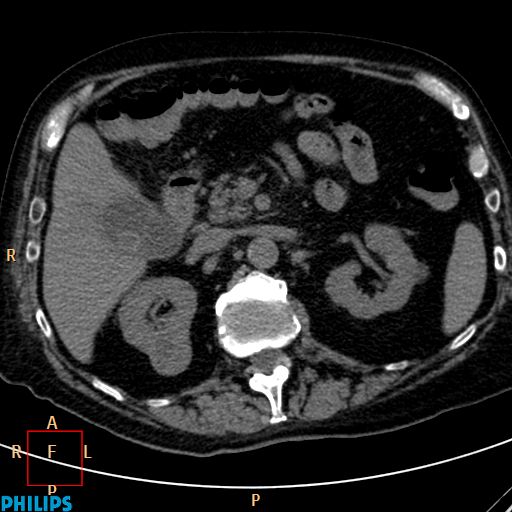

Cystosus Képlet. Kiskora óta elég sokszor fáj a feje, ezért a gyermekorvosunk az ideggyógyászati rendelés felkeresését javasolta. A szerkezet diffuse mérs.durvább, a többi régióban körülírt elváltozás nem.

A nagyerek környezete szabad, a vizsgált szintben nyirokcsomó megnagyobbodás, pathológiás kokárda nem látható. A weboldalt csak az használhatja, aki elfogadja a felhasználói feltételeket. A bal ovarium vetületében 9 mm. Hibaüzenet pedig akkor jelenik meg, ha egy képlet olyan cellákra hivatkozik, amelyeket időközben töröltek vagy más adatokra cseréltek.